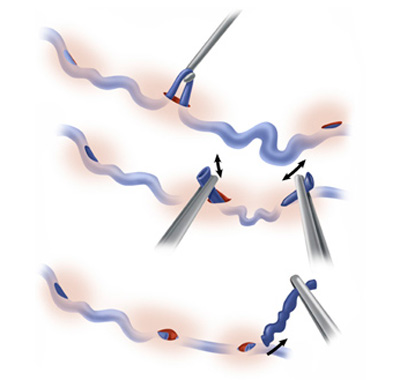

- Микрофлебэктомия. Этот вид хирургического вмешательства сочетает в себе высокую косметическую эффективность и результативность. Под местной анестезией выполняются небольшие кожные проколы, через которые удаляются поврежденные участки сосудов и варикозные узлы. Удаление вены осуществляется с помощью специального крючка, швы не накладываются, а шрамы практически отсутствуют.

Традиционная флебэктомия с использованием крючка.